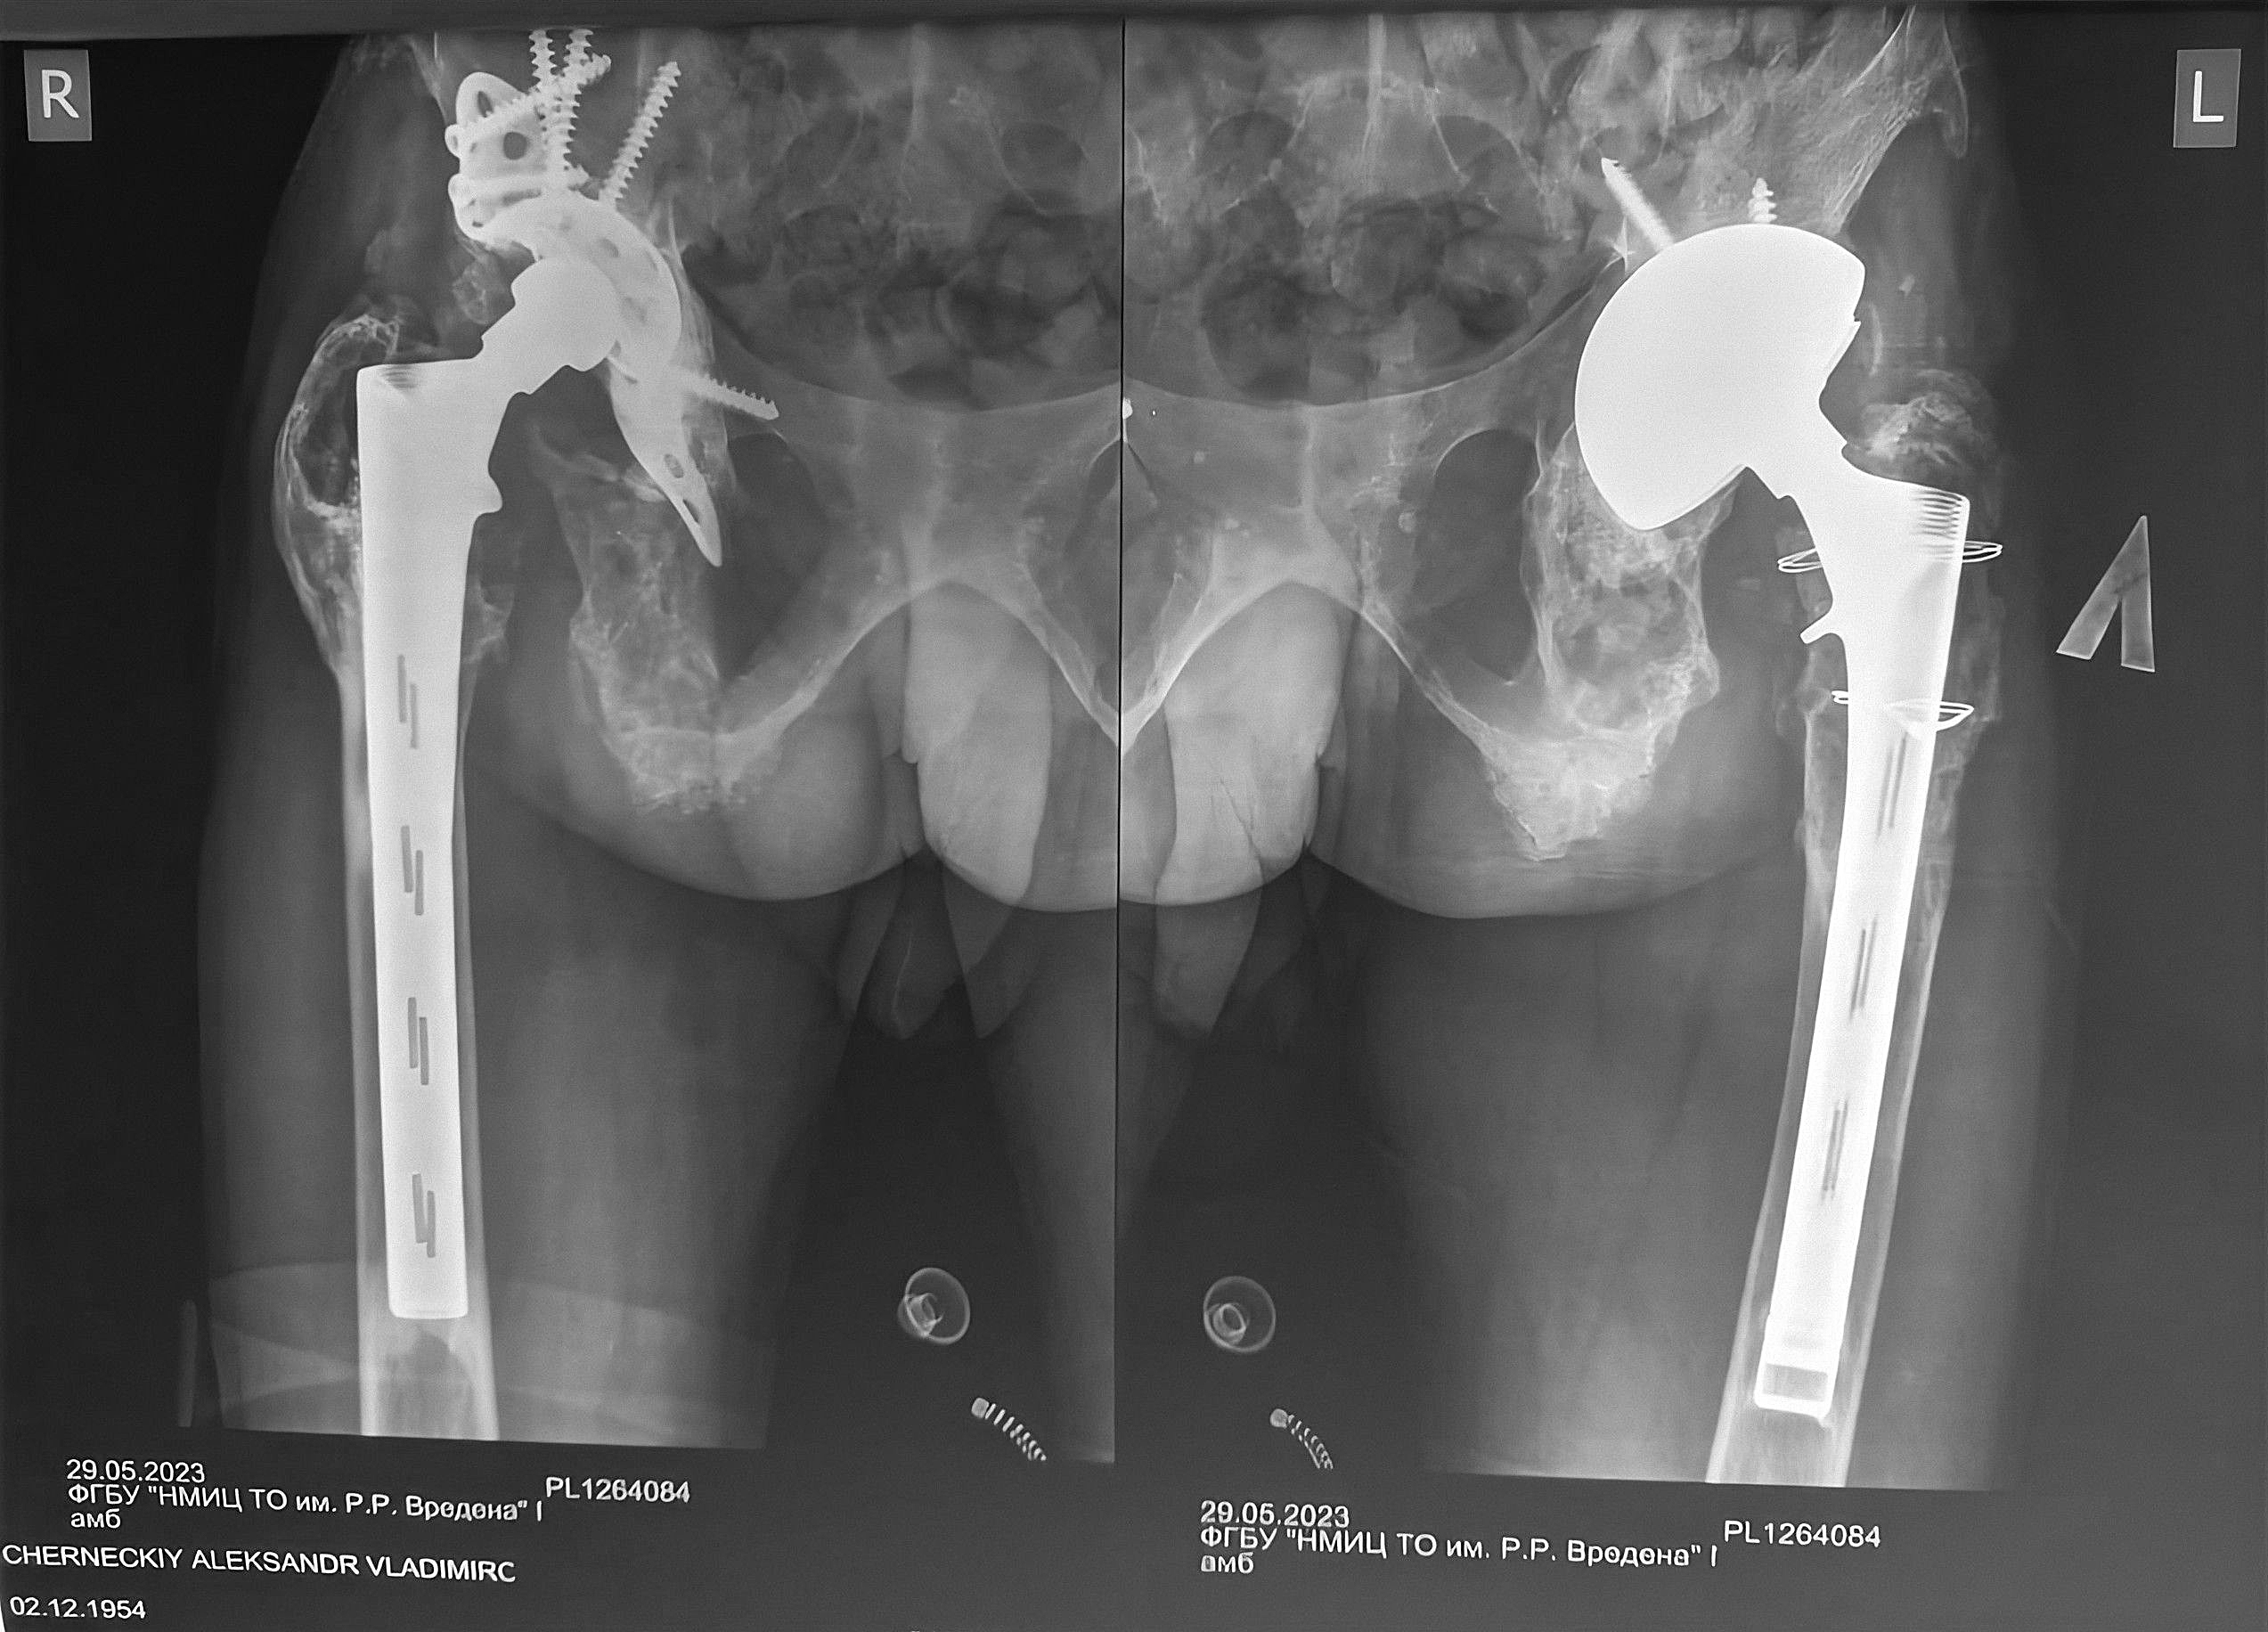

Причём, протез состоит из двух частей, из тазовой и бедренной. Одна половинка — в тазу, вторая — в бедре. Протезы Киселёва до сих пор стоят в бедренной кости. Сколько лет уже! Но они несут в себе большую опасность, потому что их вынуть практически нереально. Они длинные и врастающие. В них кость врастает так, что их вынуть, если не дай Бог придётся, — целая история. Длина конкретного протеза стандартная. Разные модели отличаются.

Да. Но это другая история. Эндопротезирование — это технологии. Наши-то, отечественные, рождались на коленке. В принципе, неплохо рождались. Технологии длинных врастающих ножек работают, но работают за счёт каких-то потерь. Эти потери заключаются в том, что, если не дай Бог, придётся протез вынимать, то это разрушение всей кости. Новый поставить — большая проблема. А вот тазовые кости у Саши не удержали протез. А во впадине всё достаточно ограничено по костной поддержке. Человек ходит, и впадина расшатывается, причём больше, чем бедренная.

Киселёв — молодец. Он был, в общем-то, продвинутым человеком и сделал для того времени неплохой протез. Но, как показала практика, западные инженеры шли вперёд с самого начала, и, конечно, опережали. Они, конечно, более работающие конструкции делали. Но тогда просто не было возможности ставить другие. Заграничные протезы широко пошли примерно с 2003-го. Тогда мы Саше на ревизии поставили уже на одну сторону частично заграничную чашку, частично нашу. Что было заграничное, то поставили. Тем не менее, вторая половина этого изобретения Киселёва работает до сих пор, и это большой успех. Потому, что у нас был опыт использования других отечественных эндопротезов. Там всё намного хуже было. Они выходили из строя через 2-3 года. Поэтому, дифирамбы Киселёву оправданы.

Чернецкому ещё до 2003 года бедренные компоненты Киселёва были установлены. Или раньше ещё, или в конце 90-х, и они до сих пор стоят, это 20-30 лет. Даже для заграничных протезов это отличный результат. А вот верхние части отдельно разрабатывались, оказались неудачными. Это вертлужная, та, что в таз вкручивается, или вставляется, или приклеивается. Совершенно разный дизайн, философия, работоспособность и они могут принципиально отличаться.